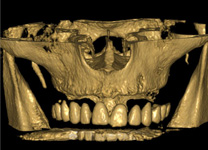

Zubní implantát, tedy v podstatě umělý zubní kořen, se zavádí do čelistní kosti a díky speciálně upravenému povrchu implantátu po určité době pevně přilne ke kosti. Tím dojde ke „vhojení implantátu“ (používá se označení osseointegrace), který se stane pevnou součástí kosti a je připraven k zatížení korunkou. Pro úspěšnou osseintegraci je však nutné přesné umístění implantátu do čelistní kosti, proto by mělo vždy každému zavedení implantátu předcházet dokonalé klinické a 3D rentgenologické vyšetření. Na základě těchto vyšetření je ve spolupráci se zubní laboratoří zhotoven finální chirurgický i protetický plán ošetření. Tento plán zahrnuje přesnou pozici, plánovanou hloubku i sklon implantátů a zhotovení chirurgické šablony pro řízenou nebo navigovanou implantaci pro perfektní finální funkční i estetický výsledek. Navigovaná/řízená implantologie operatérovi pomáhá vedením vrtáčku do kosti do přesné pozice, aby nedošlo k poranění pacienta, nepředvídatelným komplikacím nebo zavedení do nesprávné pozice. Naše pracoviště se díky bohatým zkušenostem specializuje za implantace pomocí navigace (aktivní/pasivní) již od roku 2014, kdy postupně testujeme jednotlivé systémy a materiály, které se objevují na trhu. Působíme jako vývojové, referenční a výukové pracoviště. Na vývoji a studiích přesnosti spolupracujeme s Ludwig Maximilian University of Munich (LMU), University for Digital Technologies in Medicine and Dentistry (DTMD) Luxembourg, DSI HUBER Dental Science & Innovation in Munich, Mininavident AG in Basel, CH

Principem řízené navigace pomocí chirurgických šablon je pasivní vedení zahlubovacích a rozšiřovacích vrtáčků do čelistní kosti na základě předem naplánované přesné pozice, směru, sklonu a hloubce jednoho nebo více implantátů. Chirurgicko-protetický plán vychází z 3D rentgenu čelisti, otisku zubů a dásně (scanu zubů a dásně) a finálního návrhu protetické náhrady. Na základě těchto dat je v plánovacím softwaru coDiagnostiX vytvořena chirurgická šablona, která je následně vytištěna na 3D tiskárně a použitá v den výkonu. Od roku 2014 jsme tuto metodu jako první v ČR začali využívat a nadále se podílíme na vývoji a vylepšování chirurgických šablon pro ještě přesnější a předvídatelnější výsledky.

Jedná se o externí plánovací program, spojený se zubní laboratoří a frézovacím centrem, který využívá dat získaných z 3D rentgenu čelisti, otisku zubů a dásně (scanu zubů a dásně) a finálního návrhu protetické náhrady. Tento program umožňuje tříprostorovou počítačovou simulaci při plánování pozic implantátů. Součástí programu je i databáze, ve které mohou být uloženy všechny typy implantátů od všech výrobců, včetně jejich délek, průměrů i tvarů.

Lékař si vytvoří všechny typy zobrazení potřebných pro naplánování – tedy 2D snímky (panoramatický), příčné řezy i 3D model.

Vidí zde i důležité anatomické útvary – čelistní dutinu, průběh nervu atd. Po proměření množství kosti – šířky i výšky vybere z databáze vhodný typ implantátu a umístí ho do požadované lokality. Ihned vidí jeho pozici ve všech 3 rovinách a na všech snímcích i 3D modelu. Může upravovat podle potřeby jeho pozici, sklon atd.